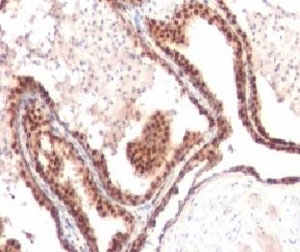

This mAb recognizes a 27kDa protein, identified as the p27Kip1, a cell cycle regulatory mitotic inhibitor. It is highly specific and shows no cross-reaction with other related mitotic inhibitors. p27Kip1 functions as a negative regulator of G1 progression and has been proposed to function as a possible mediator of TGF- induced G1 arrest. p27Kip1 is a candidate tumor suppressor gene.